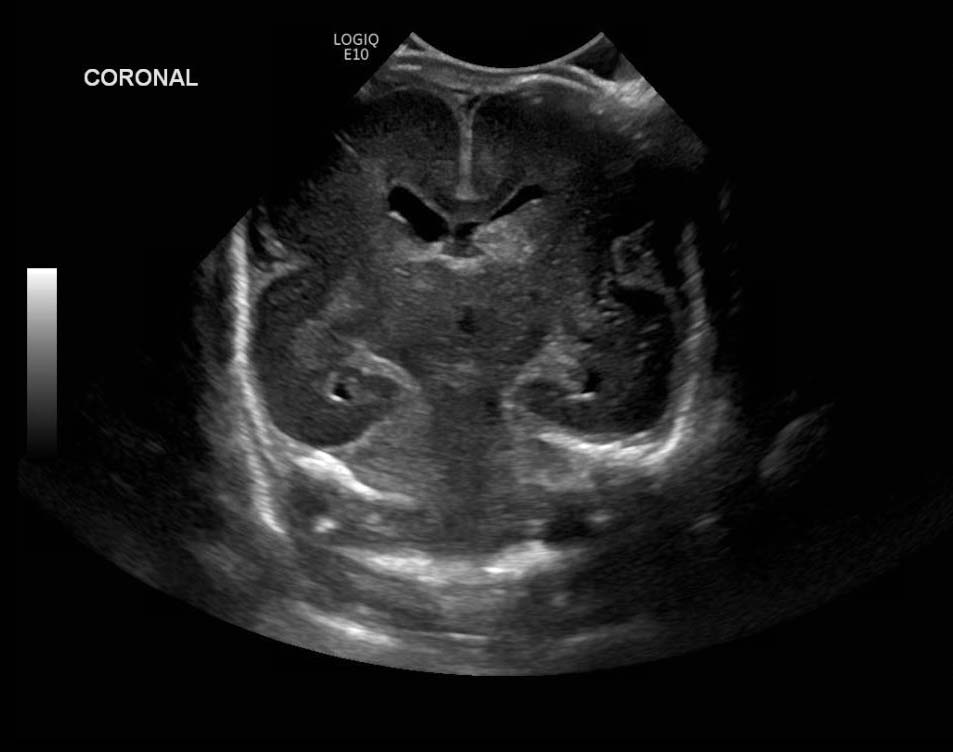

Age: 4 days (born at 24 weeks)

Sex: Male

Indication: Evaluate for germinal matrix hemorrhage

Grade 2 germinal matrix hemorrhage

Sample ReportLeft germinal matrix hemorrhage involving the caudothalamic groove and layering in the occipital horn of the left lateral ventricle without hydrocephalus (grade 2).

No abnormal brain parenchymal echogenicity or extra-axial collections.

Premature sulcation pattern.